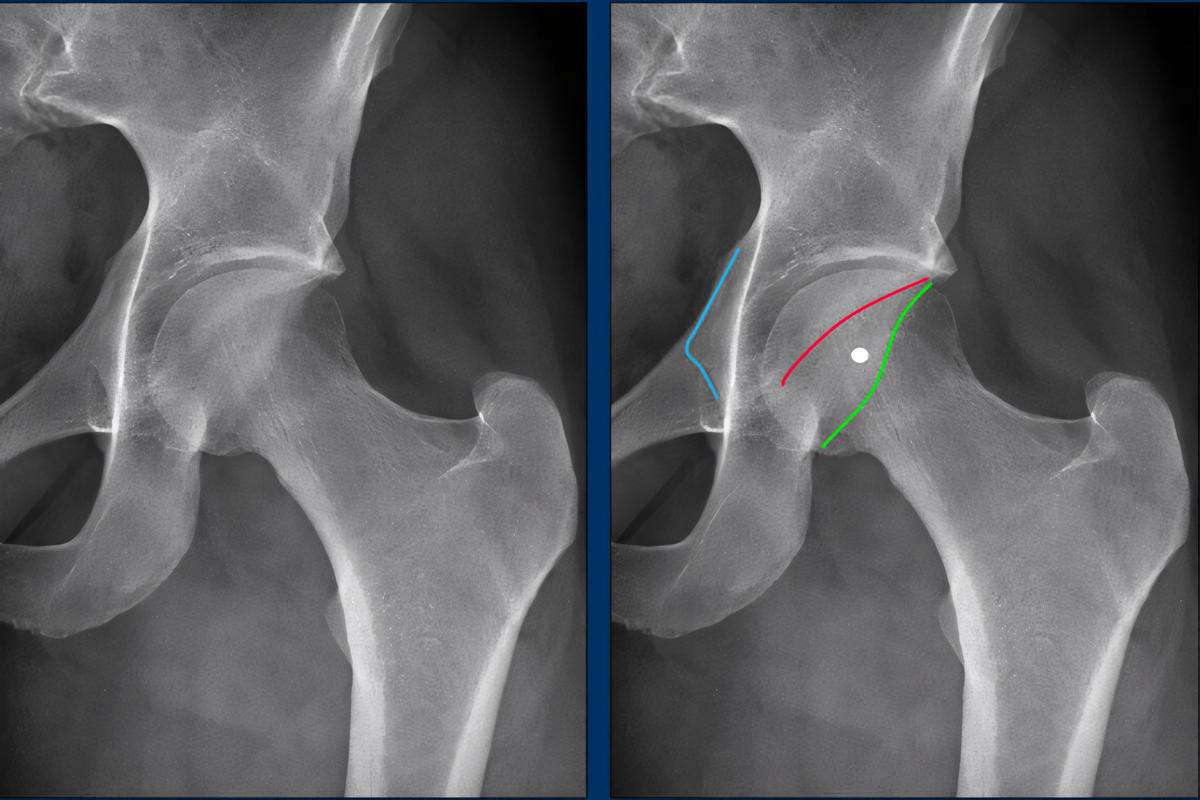

Απεικονιστικές εξετάσεις

Ακτινογραφίες λεκάνης και ισχίου για αξιολόγηση μορφολογίας

Ο σωστός απεικονιστικός έλεγχος είναι καθοριστικός για τον σχεδιασμό της θεραπείας.